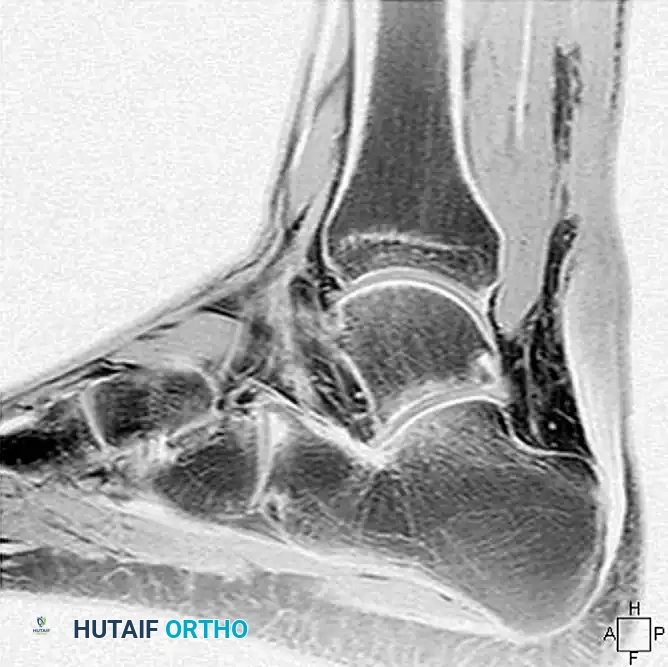

Imaging Evaluation

Magnetic Resonance Imaging (MRI) is the gold standard for evaluating chronic ruptures. It is highly helpful in estimating the exact gap between the retracted, degenerated ends of the tendon, which dictates the surgical reconstructive algorithm. Chronic ruptures appear as an area of low-intensity signal on T1-weighted images and exhibit an alteration in T2-weighted signal due to scar interposition and tendinosis.

Image